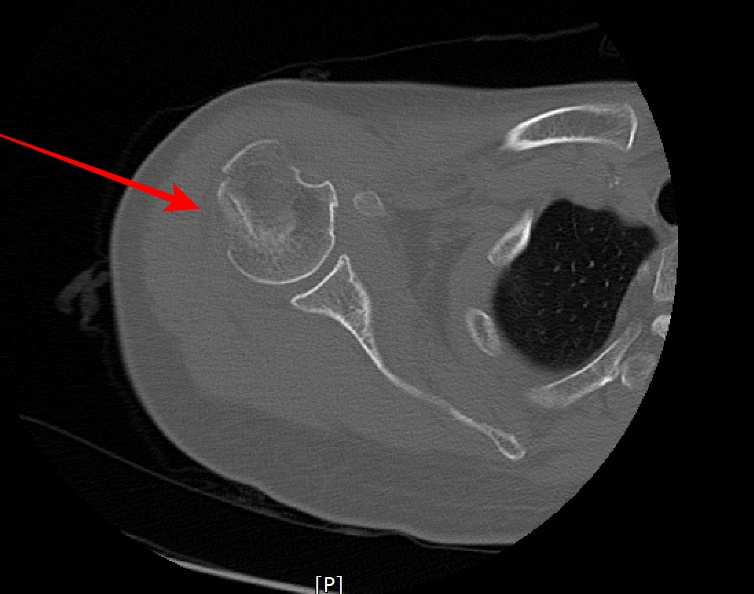

- shoulder 전체를 포함하여 scan 하였다.

- axial 영상을 획득 후 MPR로 재구성하였다.

- 붉은색 화살표가 골절된 부위다.

displaced neck fracture of humerus with impaciton